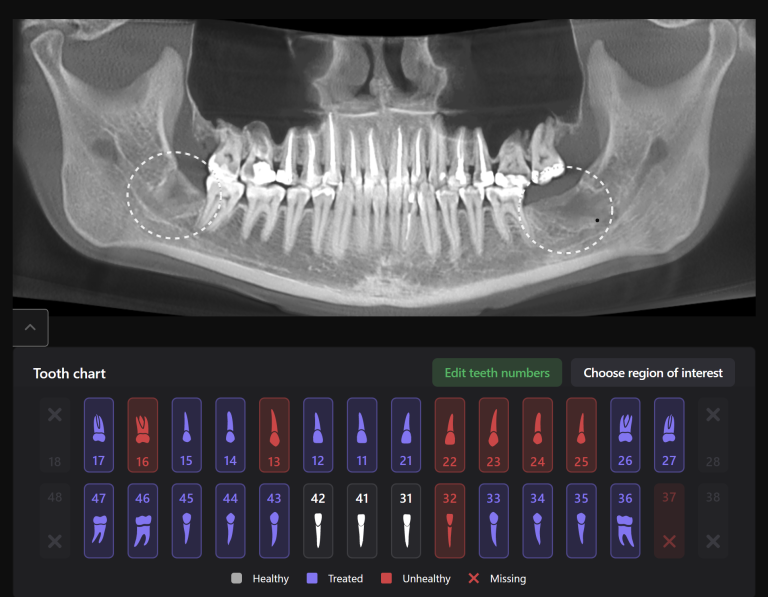

Extracting upper third molars can be difficult, if they are impacted and in contact with the maxillary sinus. Diagnocat AI will help you carefully plan your procedure, minimizing the risk of possible complications.

The “Third Molar Report” is a tool created by Diagnocat AI, it creates an optimal 3D visualization which helps to assess the position of the roots of the third molars relative to the roots of adjacent teeth and the floor of the maxillary sinus.

Teeth 18 (Universal 1) and 28 (Universal 16) were removed with minimal surgical trauma and without causing damage to the maxillary sinuses.